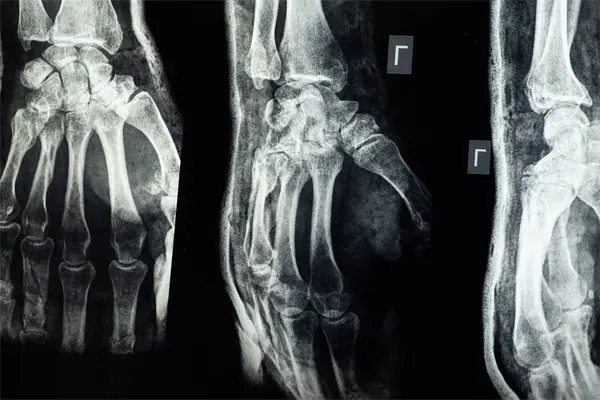

La osteoporosis en el adulto mayor es una enfermedad esquelética crónica y progresiva caracterizada por la disminución de la masa ósea y el deterioro de la microarquitectura del tejido óseo, lo que conduce a huesos frágiles y un mayor riesgo de fracturas

La osteoporosis inicialmente no produce dolor ni signos evidentes. Sin embargo, a medida que avanza, la osteoporosis debilita los huesos, aumentando el riesgo de fracturas, que son la principal manifestación clínica.

- Fracturas espontáneas o con mínimos traumatismos, especialmente en huesos largos.

Las principales consecuencias de la osteoporosis en el adulto mayor son las fracturas óseas.

- Fracturas vertebrales que producen dolor agudo o crónico en la espalda, pueden causar deformidades y acortamiento de la estatura.

- Fracturas en muñeca y clavícula que también afectan la calidad de vida y pueden limitar la movilidad y autonomía.